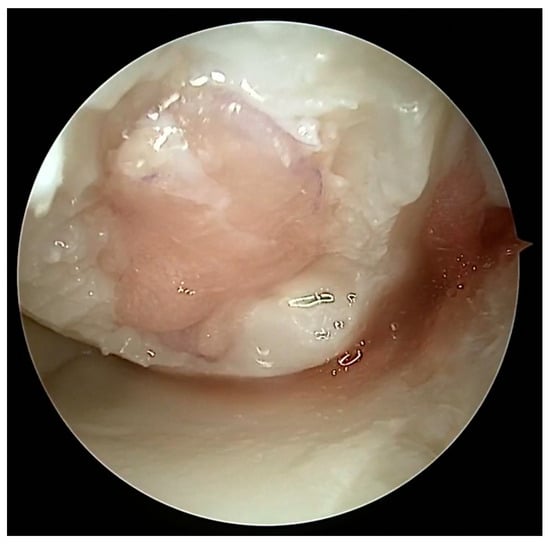

Figure 10.

Dry arthroscopy view of a biodegradable non-woven hyaluronic acid scaffold covering a cartilage defect on the medial femoral condyle.